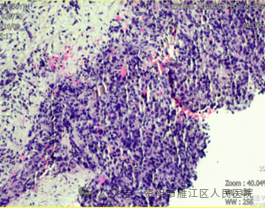

穿刺过程十分顺利,术后患者恢复良好,无明显不适症状。穿刺活检术后病理结果:考虑为低分化肝细胞癌(WHO III级)。为制定下一步治疗方案提供了重要依据。

超声引导下肝穿刺活检,可以准确定位肝内穿刺部位,对肝脏病变组织穿刺,取得活体肝组织标本,进行病理学诊断,可作为肝占位及肝内弥漫性病变诊断的“金标准”,不仅可以判断肝占位类型、分化程度、免疫组化等,更有助于评估是否用药敏感,实现对患者的“个体化”治疗。